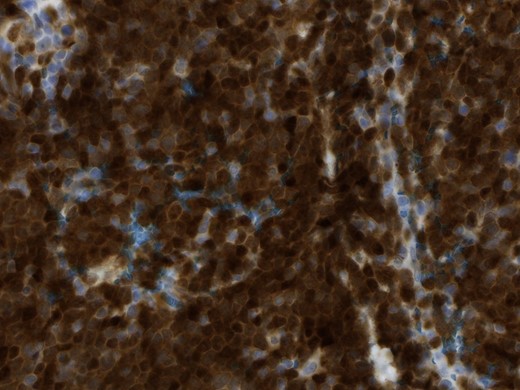

In the pathological assessment the appendix measured 10 and 4.5 cm in diameter. Histopathology revealed an infiltrating non-Hodgkin lymphoma, blastoid B-cell-type, a mantle cell lymphoma. The immunohistochemical pattern was positive for CD20, CD5, Cyclin D1, bcl-6 (that fits for blastoid type), negative for CD3, CD23 and CD10. MIB-1 was up to 75% (Figs 4 and 5).

Magnification 10×, hematoxylin and eosin staining shows a monomorphic lymphoid population with a diffuse growth pattern.

Magnification 40×, the immunohistochemical staining shows strong diffuse nuclear expression of Cyclin D1 (>95% of all mantle cell lymphoma including CD5-negative cases).